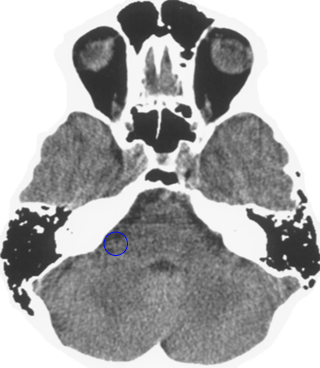

Which is the brain relais that is shown here? 25 Questions each cycle, try more!

Question 1 of 25

Middle ear mucosa left

Rectal mucosa

Coronary arteries, aortic arch, carotid arteries, bradycardia, penile sensitivity, clitoral sensitivity

Liver

Left hemispheres of the retinas

Lesser curvature of the stomach, mucosa of the bile ducts, pancreatic ducts, bulb of the duodenum